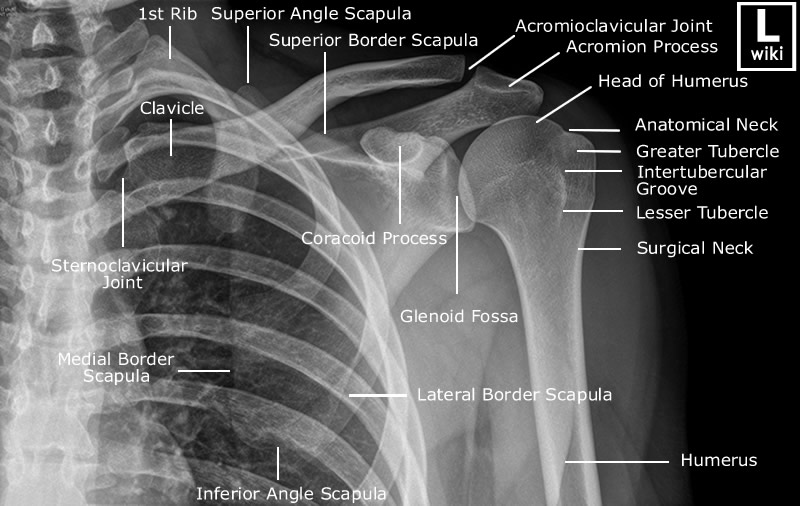

Shoulder Radiographic Anatomy

| AP View | |